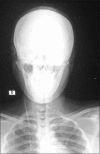

Shunt calcification is a rare complication of ventriculoperitoneal shunting that occurs years later after the initial operation this condition is rarely reported in literature. Two patients with shunt calcifications were described. The first patient was 17-year-old lady who had congenital hydrocephalus and shunted in the early infancy, she was presented recently complaining of itching of the skin along the shunt track and limitation of neck movement. The patient was then operated with removal of the old peritoneal catheter and replacing it with a new one. The second patient was 17-year-old boy originally was a case of posterior fossa pilocytic astrocytoma associated with obstructive hydrocephalus, he was operated with both shunting for the hydrocephalus and tumor removal, 6 years later he presented with shunt exposure. Calcification of the shunt tube was discovered intraoperatively upon shunt removal. Shunt calcification has been observed mainly in barium-impregnated catheters. Introducing plain silicone-coated shunt tubing may reduce the rate of this condition. The usual complaints of the patients suffering from this condition are pain in the neck and chest wall along the shunt pathway and limitation of the neck movement due to shunt tube tethering, but features of shunt dysfunction and skin irritation above the shunt may be present. In this review, plain X-ray and operative findings showed that the most extensive calcification is present in the neck, where the catheters were subject to heavy mechanical stress. Disturbed calcium and phosphate metabolisms may be involved in this condition. Shunt calcification is a rare condition that occurs due to material aging presenting with features of shunt tethering, dysfunction or overlying skin irritation. Plain X-ray is needed to detect calcification while shunt removal, replacement or endoscopic third ventriculostomy may carry solution for this condition.